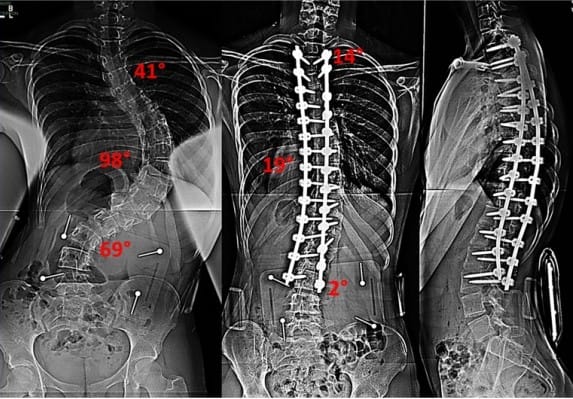

Skolioze lahko zdravimo konzervativno ali operativno. Pomembno je vedeti, da skolioze običajno spontano napredujejo, predvsem ko gre za večje krivine. Ko so skolioze še v začetnem stanju, kar pomeni, da ne presegajo 20° po Cobbu, jih zdravimo konzervativno. Pri konzervativnem…